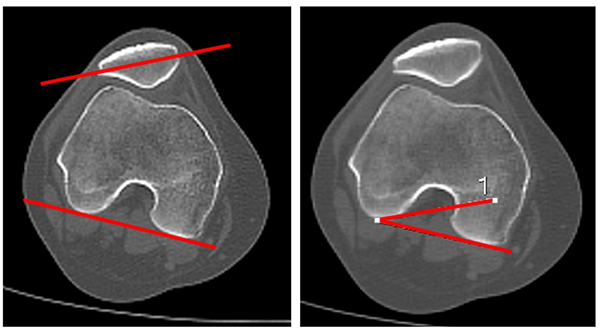

Ángulo de inclinación patelar (tilt patelar)

Esta medición se realiza en 0 y 30° de flexión de rodilla. Para el cálculo de este ángulo, se superponen las imágenes de dos cortes axiales: el corte donde se visualiza el mayor diámetro transversal de la rótula con otro corte, en el que se visualiza la escotadura intercondílea de morfología redondeada, tipo arco romano (corte de línea bicondílea). La inclinación patelar se obtendrá al medir el ángulo formado por la intersección de dos líneas: una que pasará por el centro de la rótula en su diámetro mayor, y otra que une los bordes posteriores de los cóndilos femorales (línea bicondílea). Valor normal: 10° en extensión según Galland, quien considera patológico más de 20°. La inclinación patelar varía según el ángulo de flexión de rodilla, mayor en extensión y con disminución a medida que se flexiona9, 10 (fig. 6).

Figura 6: Ángulo de inclinación o tilt patelar. Se mide con la superposición de dos cortes tomográficos: un corte que pase por el eje transversal mayor de rótula y el otro corte en fémur donde se ve figura de arco romano por la línea bicondílea. Se mide el ángulo con las líneas formadas por el eje mayor transversal de rótula y una línea paralela a bordes posteriores de cóndilos femorales. Valor normal: 10°.